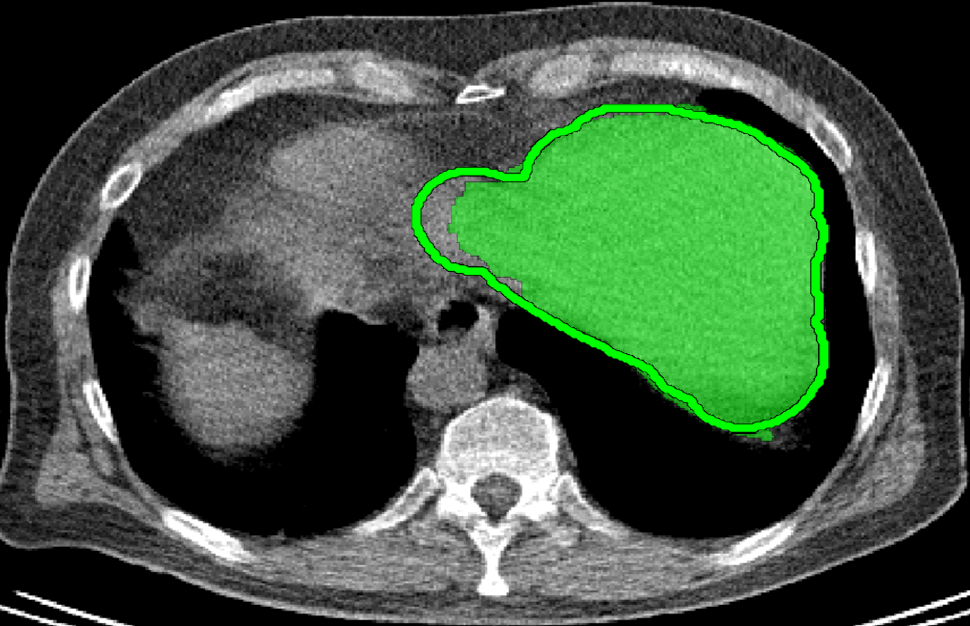

We applied our method on PET-CT scans of three different subjects to segment their liver, left kidney, right kidney and the background. Although we applied our method and Potts model on the 3D volumes we only show the results on a few representative slices from each volume in Fig.11. Also, the results of different methods for each subject were computed using the same smoothness. We can see from the last two rows which compare our method to Potts, using Hedgehogs constraints enabled us to avoid geometrically incorrect segmentations, e.g. one liver inside the other (last-row middle), or parts of left kidney is between the right kidney and liver (last-row right). Furthermore, for test subjects 1 and 2 the kidneys and background were poorly segmented by Potts model, e.g. most of the kidneys were segmented as background for test subject 1. Potts poor performance is due to the large overlap between the kidneys and background color models. This overlap resulted in an in-discriminative data term for Potts to properly separate them. This issue becomes worse in iterative frameworks where color models are re-estimated based on current segmentation. To be specific, if at any iteration Potts model resulted in a bad segmentation then re-estimating the color models will bias them towards the bad segmentation and subsequent iterations worsen the results. Comparing our results for subjects 1 and 2 to Potts model shows that our method is less prone to the aforementioned issue as we forbid undesirable segmentations, i.e. those that do not respect shape constraints.

| Subject 1 | Subject 2 | Subject 3 | |||

| Our method (Hedgehogs Shapes + Potts) | ![]() |